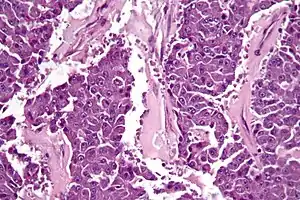

| Micrograph of an acinar cell carcinoma of the pancreas. H&E stain. | |

Histomorphologically, the tumour resembles the cells of the pancreatic acini and, typically, have moderate granular cytoplasm that stain with both PAS and PASD.[4]

Light microscopy of an acinar cell carcinoma biopsy typically shows granular appearance.[5] Immunohistochemistry is usually positive for trypsin, chymotrypsin and lipase.[5] On genetic testing, altered genes/proteins are typically found for p53, SMAD4, APC, ARID1A and GNAS.[5]